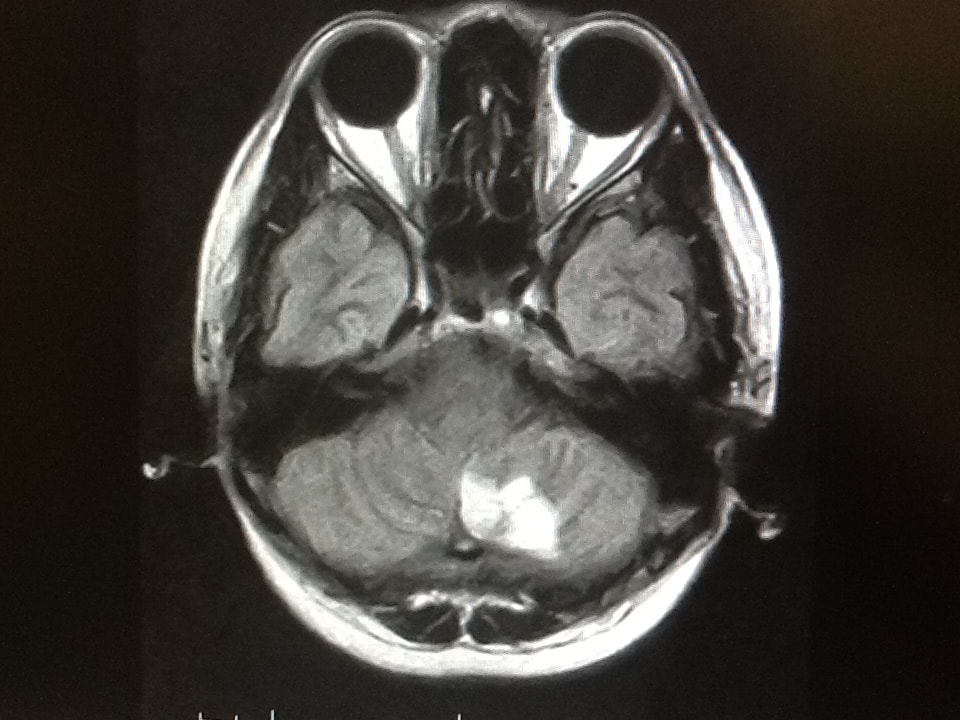

頭部MRIのフィルム

脳MRI画像

1|脳MRIドック

自覚症状がない方にも脳梗塞が生じている場合があります。この検査は痛みを伴わずに脳梗塞の有無と大きさ、場所、そしてまれに発見される脳腫瘍の有無や脳の萎縮などをチェックする検査です。

所要時間:30分  費用:22000円(消費税込み)